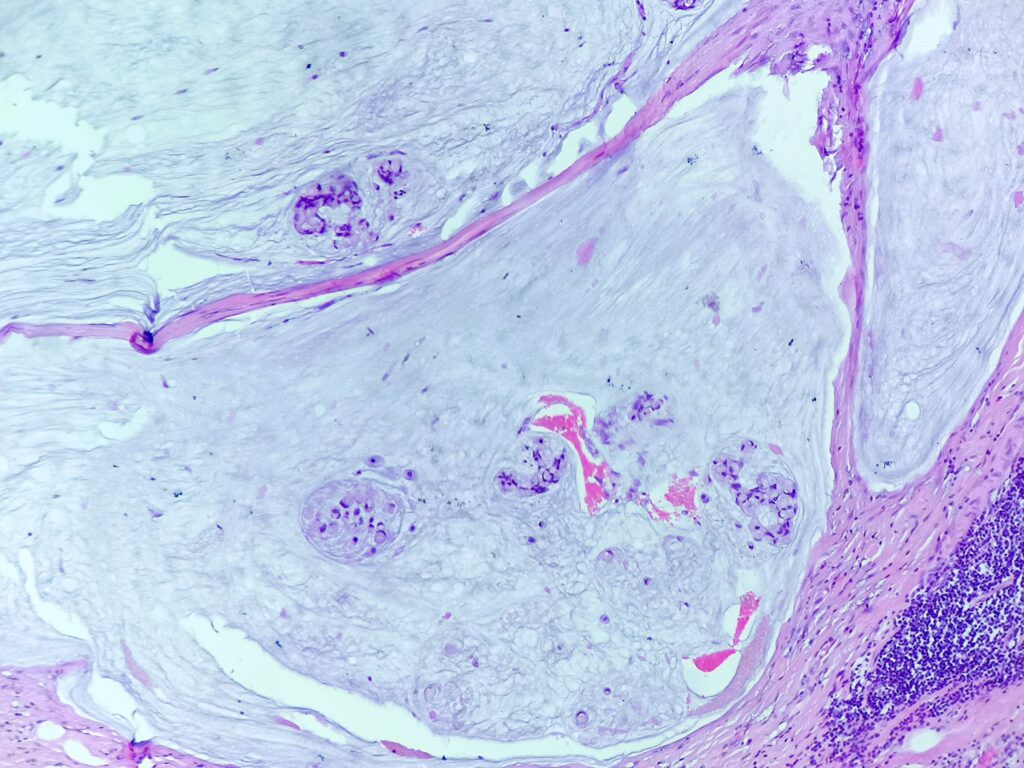

Pacjentka 61 letnia z guzem kątnicy wykrytym w trakcie diagnostyki obecności krwi utajonej w kale. Wykonano prawostronną hemikolektomię.

Do badania makroskopowego nadesłano fragment przewodu pokarmowego długości 55cm zawierający dystalny fragment jelita cienkiego długości 5cm oraz kątnicę, wstępnicę i fragment poprzecznicy. Do jelita przylega fragment sieci wymiarów 30x15x0,5cm. Na przekrojach w kątnicy, w odległości 2cm od zastawki krętniczo- kątniczej oraz około 45 od dystalnej linii odcięcia obecny jest płasko- wyniosły guz wymiarów 5×4,5×1,5cm, który w ocenia makroskopowej jest ograniczony do mięśniówki właściwej, nie nacieka przylegającej tkanki tłuszczowej ani surowicówki.

Obrazy mikroskopowe: